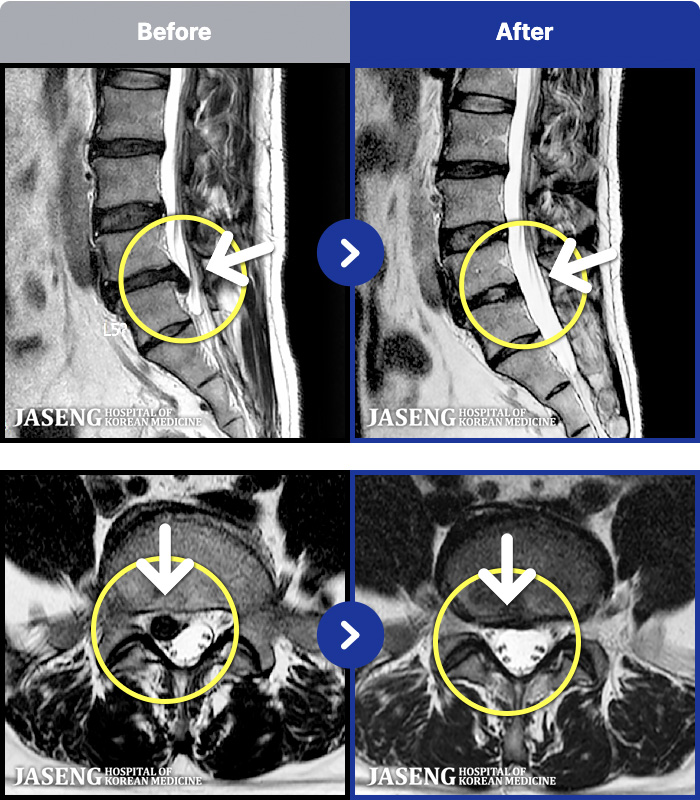

- MRI ġ

MRI ġ

191 MRI ũ ʸ Ȯϼ.

[_㸮ũ] 㸮 ٸ ϰ ϻȰ Ұ߽ϴ.